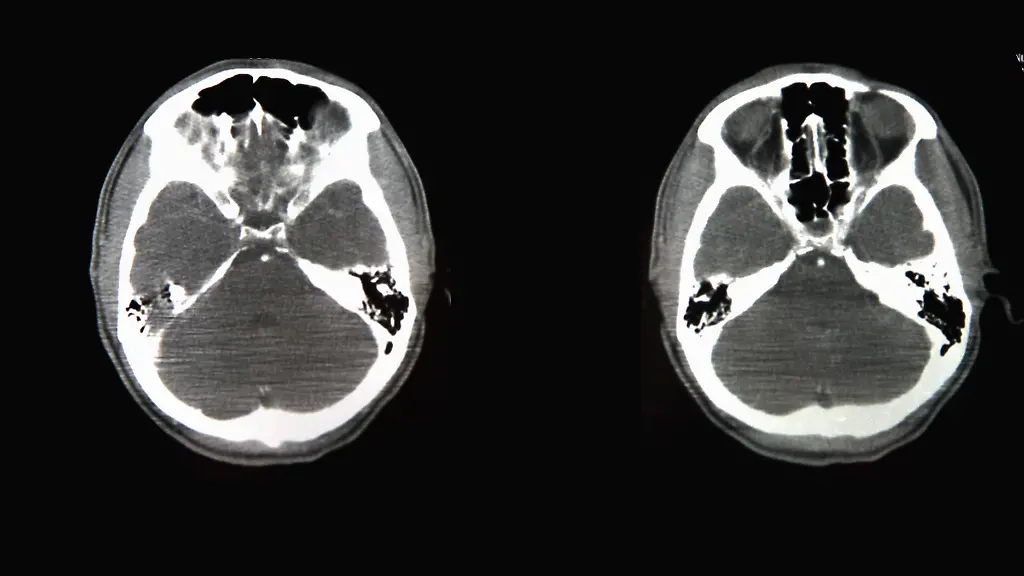

Die fünfjährige Tafida leidet an einer schweren Schädigung des Gehirns. Die Ärzte am Royal London Hospital sehen keine Überlebenschance und wollen die Geräte abstellen. Doch die Eltern möchten ihre Tochter in Italien weiter behandeln lassen. Nun landet der Streit vor Gericht.

"Die Eltern glauben, dass jede Behandlung bereitgestellt werden muss und es Gottes Aufgabe ist, das Leben zu nehmen - und nicht die der Menschen", erklärt der Anwalt der Familie der Zeitung. "Es gibt keine Hinweise darauf, dass Tafida durch eine Auslandsreise Schaden erleidet, und ihre Eltern haben das Recht, sie in ein anderes Krankenhaus zu überweisen", sagte er dem britischen "Standard". Tafida war im Februar kollabiert und erlitt dabei schwere Schäden am Gehirn. Vor dem Zwischenfall war sie nach Angaben der Eltern ein völlig gesundes Kind.

Seitdem liegt sie jedoch im Koma und ist auf Beatmungsgeräte angewiesen. Laut Aussagen der Eltern soll sie allerdings auch kleine Anzeichen der Genesung zeigen. Das Mädchen liegt mittlerweile seit mehr als vier Monaten auf der pädiatrischen Intensivstation.